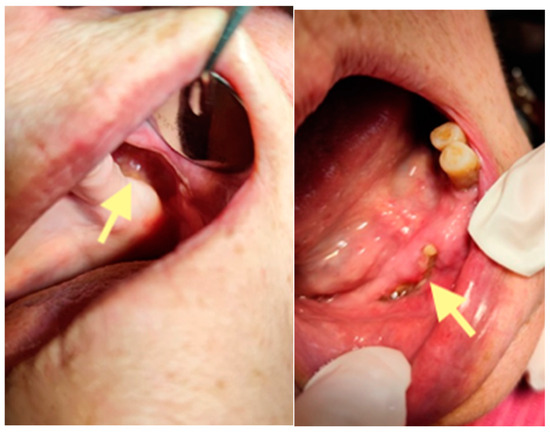

Figure 6.

Control visit of the patient after the second surgery, one month after the second operation performed on 28 May 2025.

However, on 29 September 2025 (last control visit), we noticed complete healing in both areas of the lower jaw. The patient could use a new partial plate for the lower jaw.